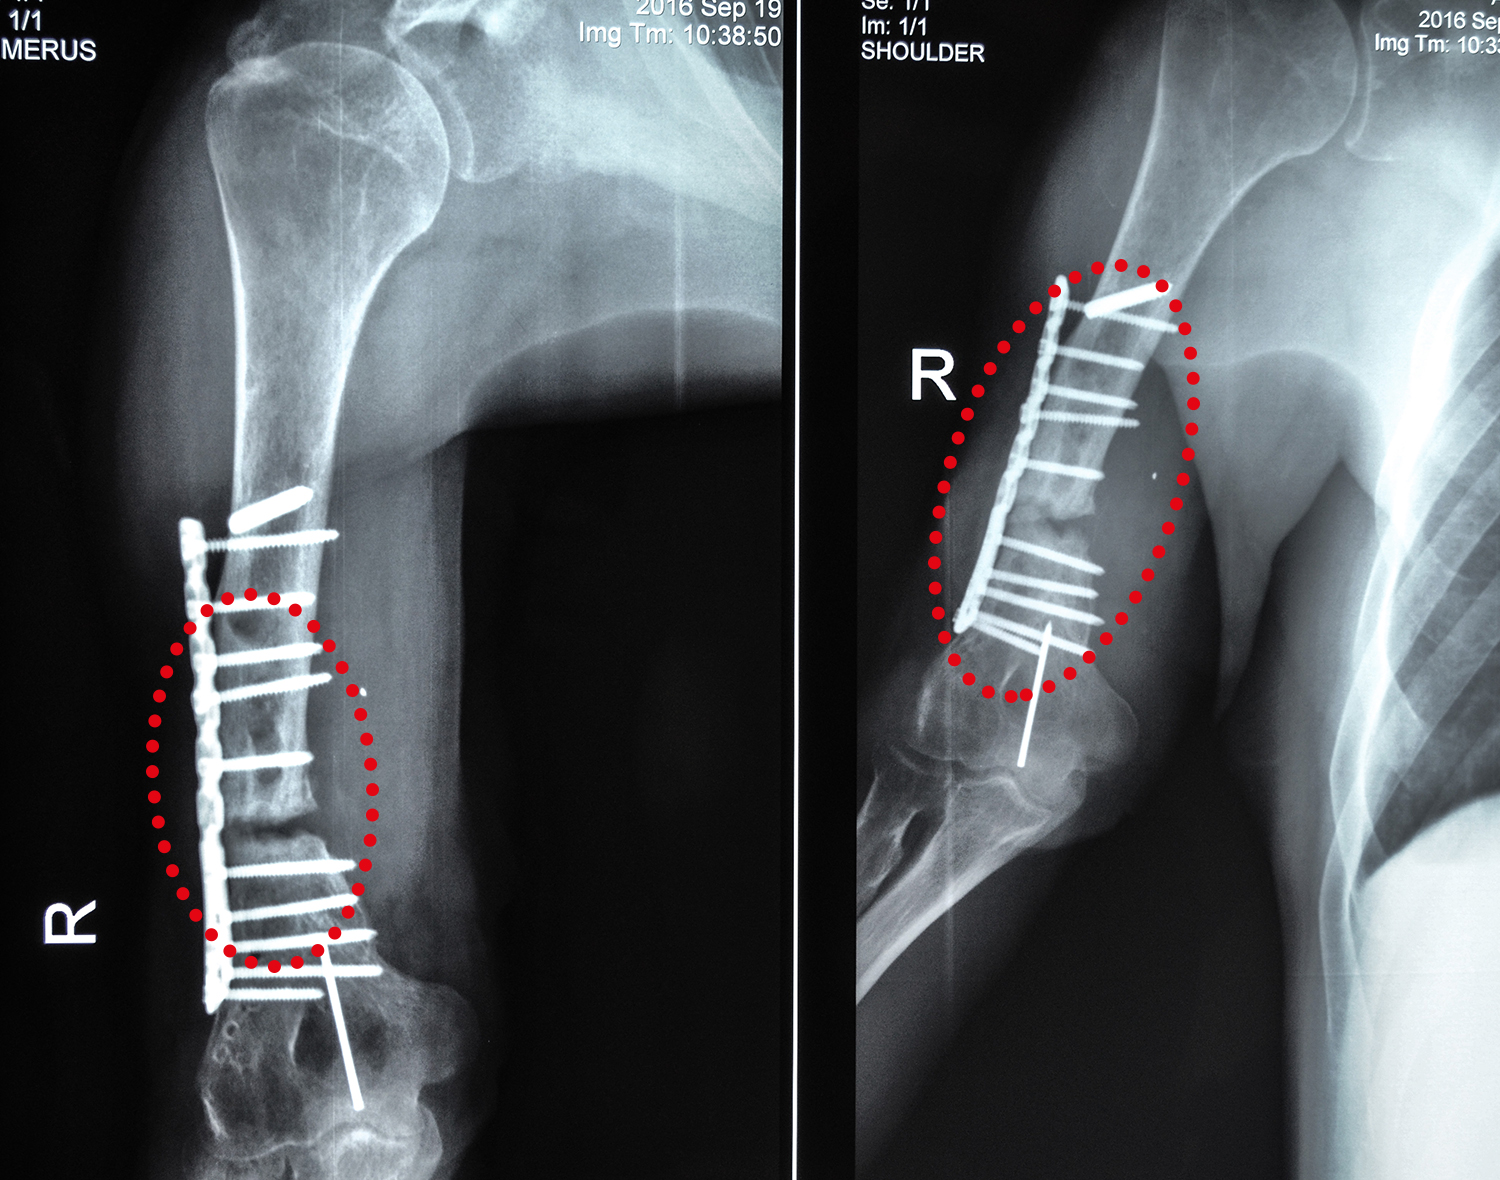

Василь Михайленко — 42-річний малинчанин. До початку війни на Сході працював на паперовій фабриці. На війну потрапив майже з перших днів, його мобілізували у березні 2014 року, ще у першу хвилю. Під час служби в АТО встиг взяти участь у боях біля Андріївки, Амбросіївки, Сонячного. Тривалий час підрозділи бригади брали участь у обороні району біля Савур-Могили. Саме там у серпні 2014 Василь і отримав важке поранення руки. Під час обстрілу, біля с. Степанівка, осколок влучив у праву плечову кістку. Того разу поранень зазнало чимало побратимів Василя.

Боєць лікувався у госпіталях Дніпра, Одеси, Києва та Ірпеня, переніс чотири операції. Два рази на розтрощену кістку ставили пластину, утім, за два роки вона так і лишається незрощеною. Усвідомивши що перед ним постала загроза інвалідності, Василь, за порадою волонтера Наталії Романенко, звернувся до клініки Ілая в рамках проекту “Біотех-реабілітація поранених”.

Фахівці клініки планують підготувати місце перелому до імплантації, виростити із власних тканин Василя новий шматок кістки та заповнити місце ураження власними стовбуровими клітинами чоловіка. З часом імплант зростеться із кісткою у моноліт, і Василь зможе знову рухати власною рукою. Технологія досить нова, та її вже успішно застосували для більш ніж сімдесяти тяжкопоранених пацієнтів проекту. От тільки фінансувати це лікування вчергове будуть лише благодійники.